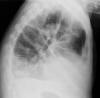

Fractura costal

Fractura costal por caída.

Paquipleuritis. Fractura costal.